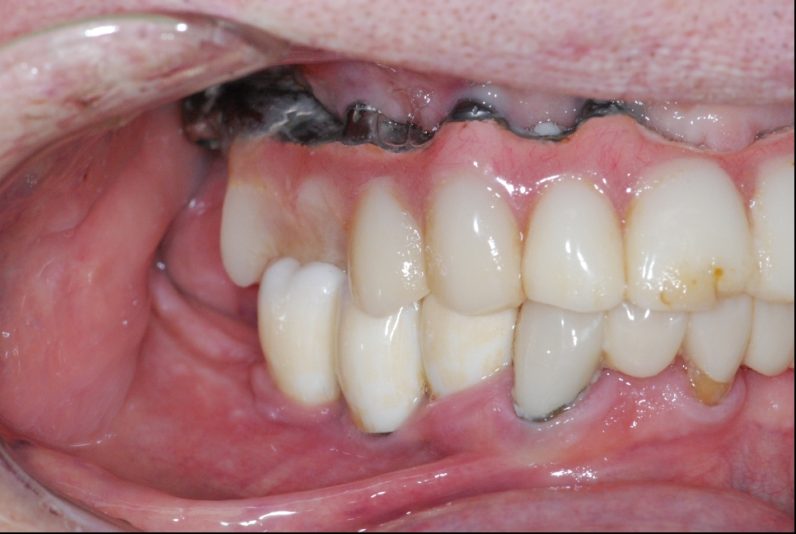

Hey, I will be removing this hybrid denture for replacement. I am having a difficult time locating the access screws for removal. Can anyone please help me find them? Implants are placed at site 3,5,7,9,12,13,15. Thank you for your help!

It is always a bit tedious and a pain but typically using various X-rays and especially a pano can give you areas to try to access slowing until you find all the screws, slow and patience is keep to not over prep into the screws

Use air and really dry the acrylic but you can see the outline of the access on the occlusal of 5,6. I would block enough time and just go slow. Best part is since the prosthesis is plastic it’s easily repairable. U got this.